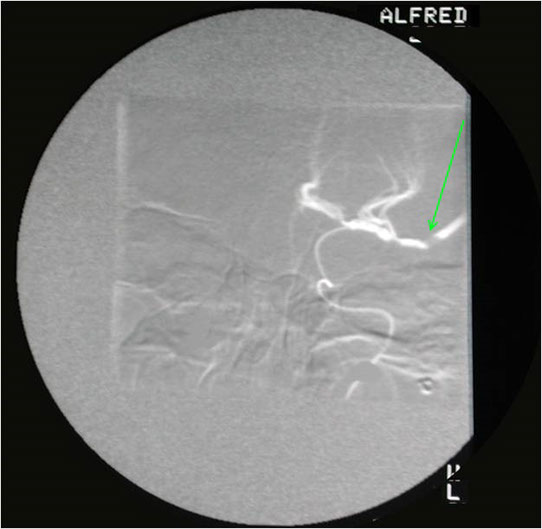

However, the graft again stenosed as you can see. Fibromuscular dysplasia may affect many arteries and here the arrow is pointing to disease of the right common iliac artery in the same patient.